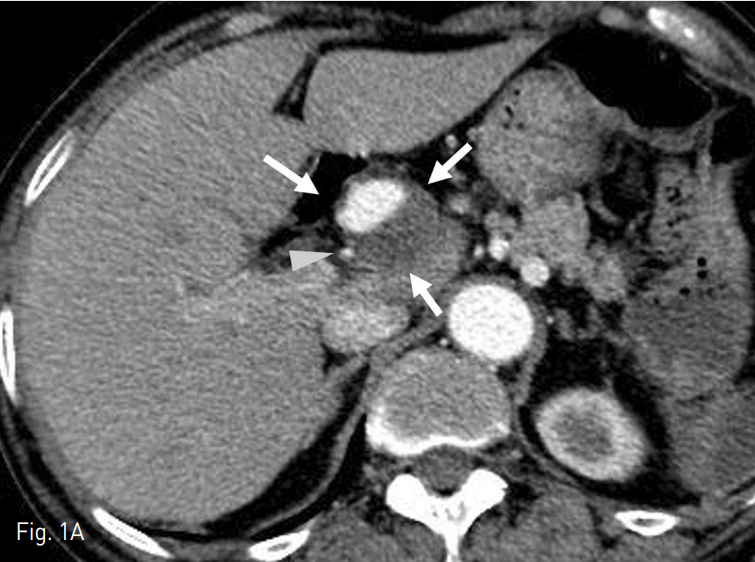

CT에서 proper hepatic artery에 wide neck을 가지고 있는 직경 3cm의 aneurysm이 있으며, 내부는 일부 thrombi로 차있음 (Fig. 1).

Fig. 1

Axial (A) and Coronal (B) CT images showed partially thrombosed aneurysm (arrow) at the proper hepatic artery (arrow head).